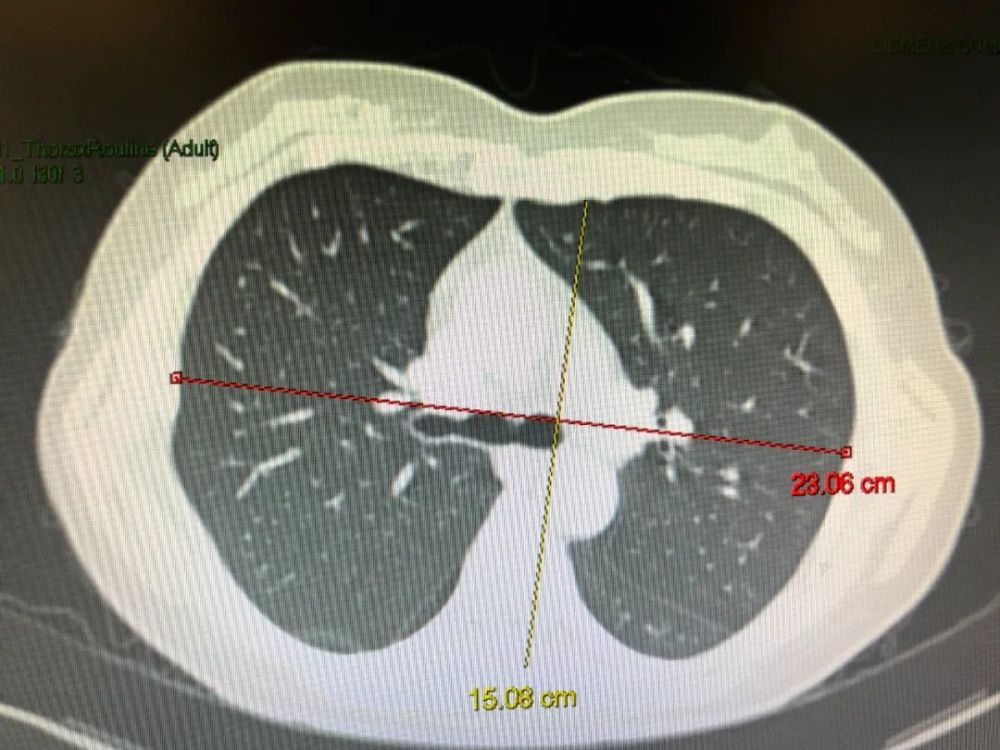

患者男,55岁,呼吸困难,气喘,查体桶状胸体症,ct如图,最可能的诊断是()

患者男,55岁,呼吸困难,气喘,查体桶状胸体症,ct如图,最可能的诊断是a.